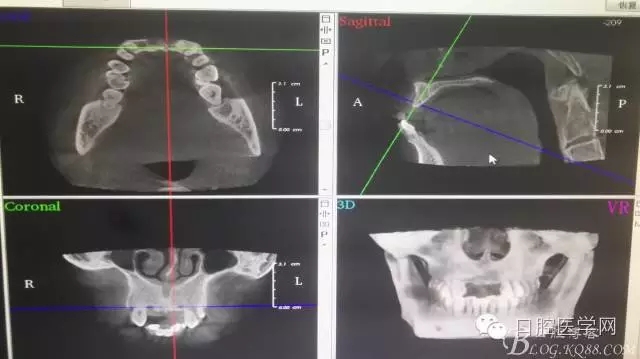

一例上前牙缺失后GBR骨再生技術

為他院轉診患者。男,無吸煙史,前牙因齲壞治療后,外力折斷導致拔除?,F拔除該牙后兩個多月。 左上區(qū)域骨寬度不足,計劃植入種植體同期GBR。

左上區(qū)域骨寬度不足,計劃植入種植體同期GBR。